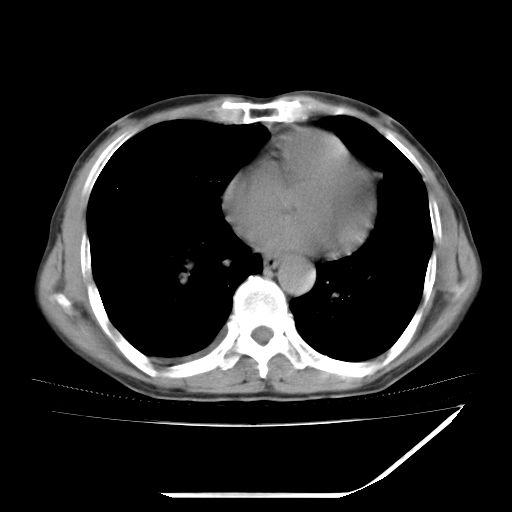

男,59岁,“结核性胸膜炎”30余年,胸部经常疼痛,多次x检查提示“肺部”炎症。腹部疼痛5日,b超提示:“肝内短管结石,余显示不清,建议进一步检查。”

两肺结核并右侧胸腔积液;脾脏、腹腔及腹膜后淋巴结结核[陈旧性];肝内胆管结石

胸部腹部都是结核(双肺。纵隔淋巴结,肝脏,脾脏,肠系膜)

两肺结核并右侧胸腔积液;脾脏、腹腔及腹膜后淋巴结结核[陈旧性];肝内胆管结石。直肠息肉?